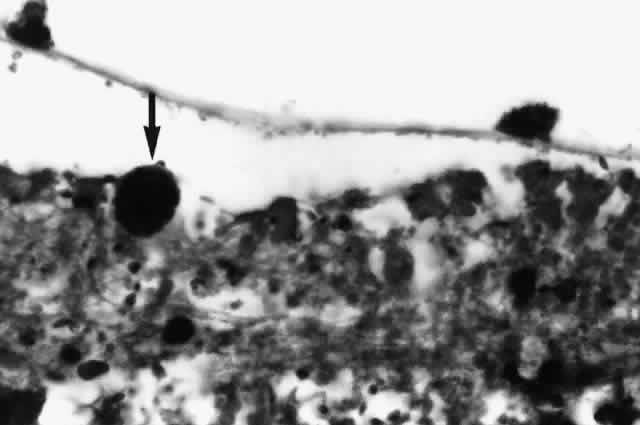

Histologic studies of AIDS-related CMV retinopathy demonstrate the tissue necrosis and cytomegalic cells characteristic of all CMV infections (Fig. 1).9,17 Electron-microscopic and immunochemical studies have identified CMV viral particles and antigen in a patchy distribution throughout all layers of the retina and occasionally in contiguous retinal pigment epithelial cells.9 Viral antigens are only rarely identified in the choroid.9,18 Viral antigen in the choroid has been found in association with vessels and is not always adjacent to areas of retinopathy, suggesting that the virus reaches the choroid through independent hematogenous spread rather than by extension of infection from the retina.

Among cases of AIDS examined at autopsy, 22% to 50% of those with CMV retinopathy have neutrophilic infiltrates in retinal tissue.9,19 This finding is atypical when compared with CMV retinopathy in non-AIDS patients, in which only a sparse lymphocytic infiltrate is observed. The difference has been attributed to intact granulocyte function and chemotaxis in patients with AIDS, in contrast to infants, organ transplant recipients, and patients with malignancies who can have more severe quantitative or qualitative granulocyte dysfunction.9 It has been noted that patients on immunosuppressive drugs can develop marked inflammatory reactions to CMV retinopathy when such drugs are withdrawn.14 Acute inflammatory cells may extend into the adjacent choroid despite the absence of identifiable viral antigens.9 The vitreous usually remains remarkably free of inflammatory material, despite the presence of virus in the vitreous cavity.20